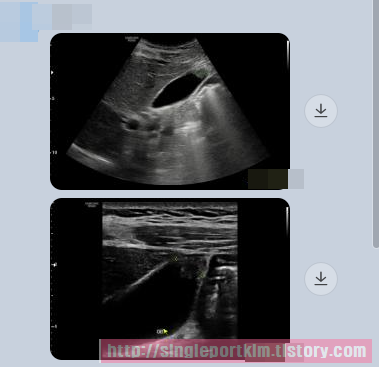

최근 동네 내과에서 복부초음파 검진시 담낭선근종증 의증인데 크기가 큰편이라며

큰 병원에 방문해 보라는데 사진상 절제가 필요한지 판단이 가능하실까요?

안녕하세요 김정윤 원장입니다. 담낭 선근종증은 담낭벽에서 자라는 혹입니다.

선근종이 자랄수록 담낭벽이 두꺼워지져 담낭 수축 능력이 줄어 들게 됩니다.

담낭 기능이 저하되면 담낭은 소화와 관련되기에 소화 능력 저하 그리고

담낭 수축력 저하에 의한 담낭내 담즙 정체에 의한 담석이 생길 경우 해당

담낭은 더이상 사용이 어렵다고 판단되어 수술적 절제를 하게 됩니다.